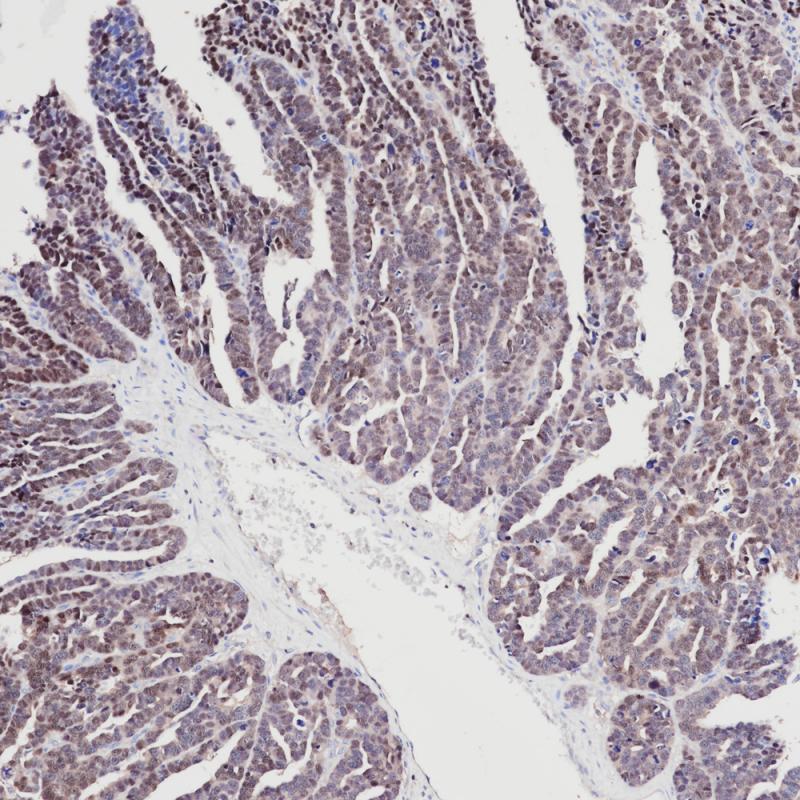

PAX-8是PAX家族转录因子的成员,在胚胎发育的器官形成中发挥重要的作用。PAX-8表达于正常的甲状腺及其相关的肿瘤,输卵管和卵巢囊肿的非纤毛黏膜细胞。临床上,PAX-8可用于肾原发上皮性肿瘤与转移性肿瘤的鉴别,也可用于卵巢浆液性癌与粘液性癌和间皮瘤的鉴别

阳性对照

浆液性卵巢癌

亚细胞定位

细胞核